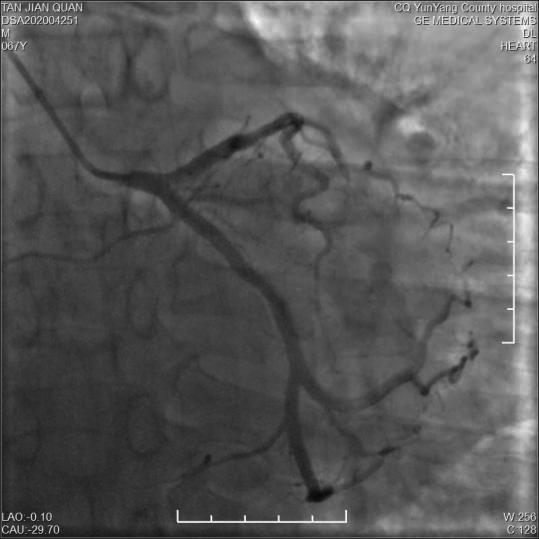

• 疑似雷帕霉素药物洗脱支架术后Kounis综合征1例

2024, 49(1):97-100. DOI: 10.13406/j.cnki.cyxb.003409

摘要 (42) HTML (15) PDF 1.14 M (104) 评论 (0) 收藏

摘要: